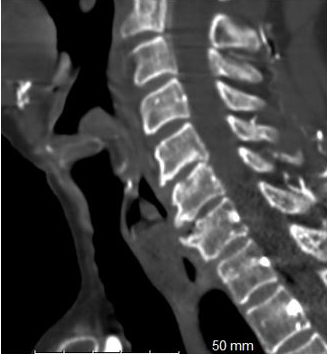

Figure 2. Sagittal views of C6-C7 anterior osteophyte.

Laboratory tests—including complete blood count, basic metabolic panel, liver panel, and lipase—were within normal limits. A chest X-ray revealed no radiopaque foreign bodies. A contrast-enhanced computed tomography (CT) scan of the neck and chest identified a 3.0 × 1.2 × 1.7 cm food bolus (Figure 1) lodged at the C6–C7 level, adjacent to an anterior C6–C7 osteophyte (Figure 2).

The current literature focuses on the ability of CT imaging to help establish the diagnosis of esophageal foreign bodies and reduce subsequent complications of a relatively frequent emergency department complaint. Not only did CT imaging help establish the diagnosis of an esophageal food impaction in our patient but also provided further information regarding the anatomical environment of the site where the patient had frequent and recurrent food impactions. Evaluation of the surrounding anatomy using CT imaging established a diagnosis of an anterior osteophyte at the level of the food impaction which gave further information for endoscopic and/or surgical planning prior to intervention.